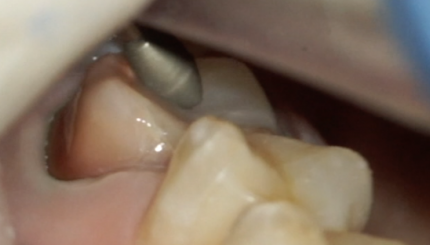

14 зуб-полная коронка.13 обратимый пульпит